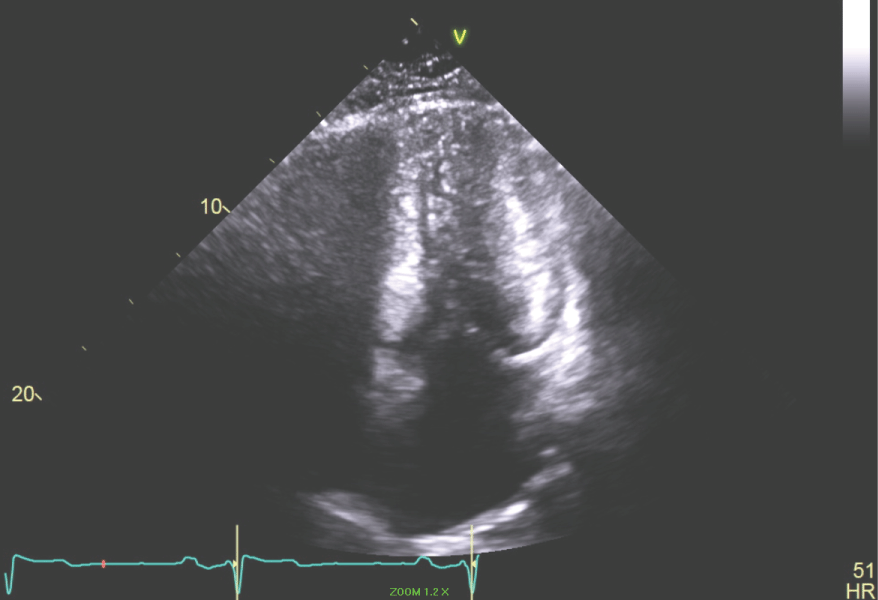

Past Medical History: The patient has a history of gene-negative hypertrophic cardiomyopathy (HCM). In 1983 at age 16 years he had a syncopal episode while playing basketball and was identified to have HCM by echocardiography (Figure 5, Figure 6, Figure 7 and Figure 8). In 2002 the patient had another syncopal episode was found to have non-sustained ventricular tachycardia on Holter monitoring. He had an ICD placed. He had hypertension, coronary artery disease, HCM, hyperlipidemia, syncope, NSVT and post-myocardial infarction VT that was managed with shock therapy.

Figure 5: The Parasternal Long axis of the LV revealing a 17 mm septum in a patient with HCM. View Figure 5

Figure 6: Apical 4 chamber view of the LV showing small LV cavity. View Figure 6